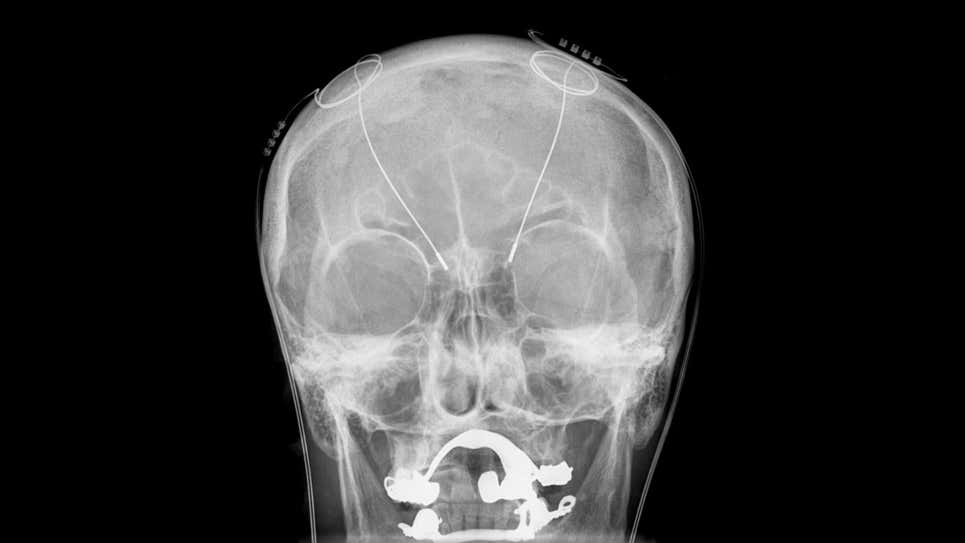

La mujer, que había estado viviendo con depresión desde la infancia, dijo que el dispositivo similar a un marcapasos le ha permitido reconstruir su vida